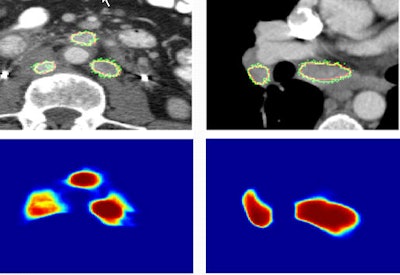

Boundary neural fields delivered the highest quantitative results, with a mean Dice coefficient between segmented and ground truth lymph-node volumes of 82.1% ± 9.6%, compared with 73% ± 17.6% for HNN-A, 69% ± 22% for dense CRFs, and 67.3% ± 16.8% for graph cuts.

Images show two examples of BNF-based lymph-node segmentation. At left are three retroperitoneal lymph nodes accurately segmented by BNF (green). The reference standard is the red curve. At right are mediastinal and right hilar adenopathy accurately segmented by BNF (green). The bottom row shows corresponding BNF probability maps. Images courtesy of Dr. Ronald Summers, PhD.A paired t-test comparing ground truth with segmented lymph-node volumes produced the following p-values: 0.87 for BNF, 0.37 for HNN-A, 0.10 for dCRF, and less than 0.01 for GC, the authors wrote in an abstract.